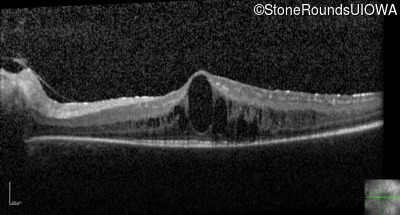

Optical Coherence Tomography - Left - 20/50 -3

Exemplar / OCT Stack